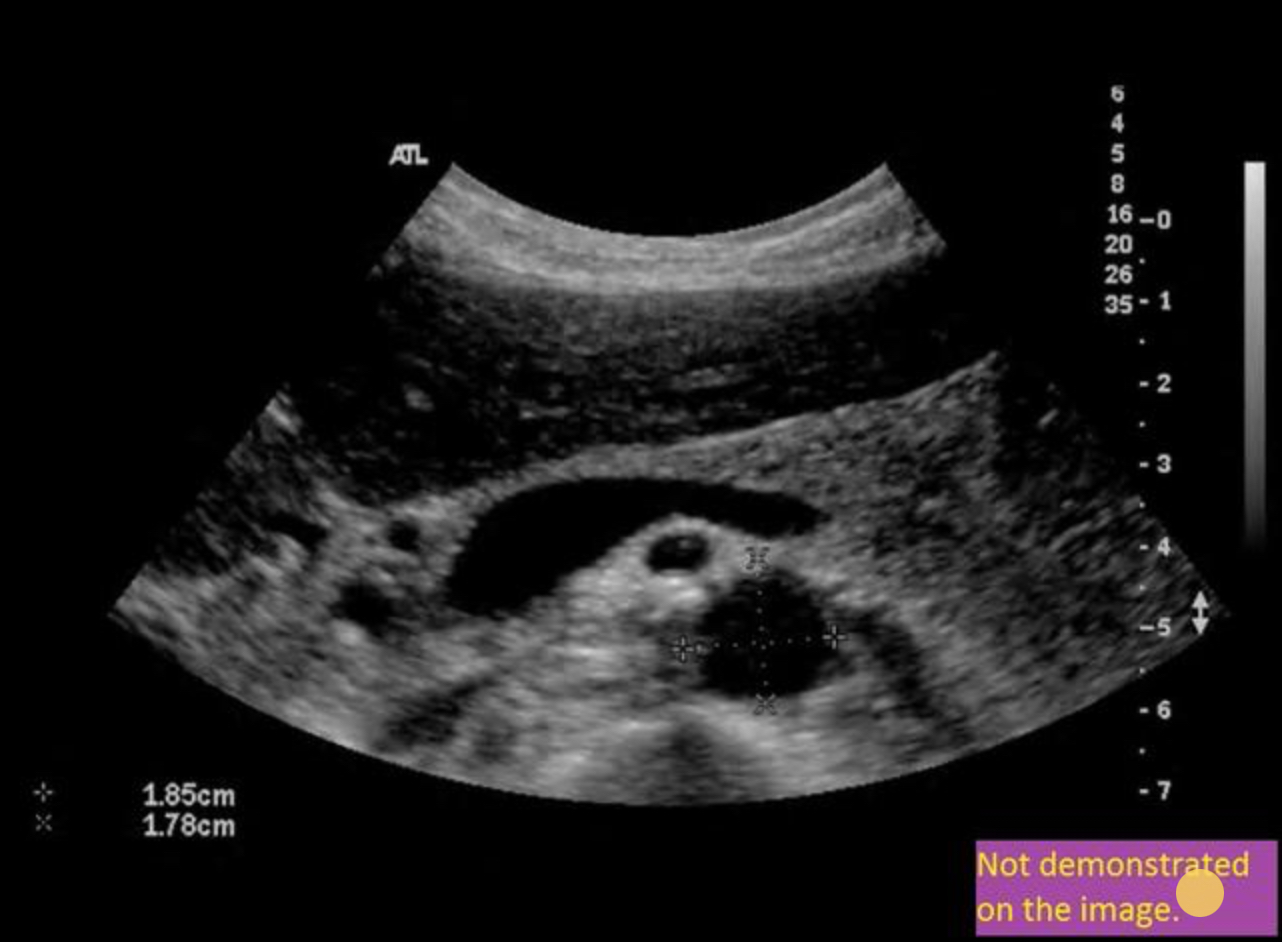

Use your mouse to place your cursor over the superior mesenteric vein and click to mark the vessel if the vessel is not demonstrated on the image, mark the purple box that says “not demonstrated on the angle”.

Which of the following can be used to differentiate Reidel lobe from hepatomegaly?